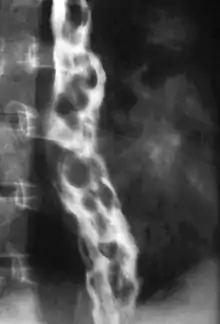

Esophageal varices are extremely dilated sub-mucosal veins in the lower third of the esophagus.[1] They are most often a consequence of portal hypertension,[2] commonly due to cirrhosis.[3] People with esophageal varices have a strong tendency to develop severe bleeding which left untreated can be fatal. Esophageal varices are typically diagnosed through an esophagogastroduodenoscopy.[4]

The upper two thirds of the esophagus are drained via the esophageal veins, which carry deoxygenated blood from the esophagus to the azygos vein, which in turn drains directly into the superior vena cava. These veins have no part in the development of esophageal varices. The lower one third of the esophagus is drained into the superficial veins lining the esophageal mucosa, which drain into the left gastric vein, which in turn drains directly into the portal vein. These superficial veins (normally only approximately 1 mm in diameter) become distended up to 1–2 cm in diameter in association with portal hypertension.

Normal portal pressure is approximately 9 mmHg compared to an inferior vena cava pressure of 2–6 mmHg. This creates a normal pressure gradient of 3–7 mmHg. If the portal pressure rises above 12 mmHg, this gradient rises to 7–10 mmHg.[5] A gradient greater than 5 mmHg is considered portal hypertension. At gradients greater than 10 mmHg, blood flowing through the hepatic portal system is redirected from the liver into areas with lower venous pressures. This means that collateral circulation develops in the lower esophagus, abdominal wall, stomach, and rectum. The small blood vessels in these areas become distended, becoming more thin-walled, and appear as varicosities.

In situations where portal pressures increase, such as with cirrhosis, there is dilation of veins in the anastomosis, leading to esophageal varices.[3] Splenic vein thrombosis is a rare condition that causes esophageal varices without a raised portal pressure. Splenectomy can cure the variceal bleeding due to splenic vein thrombosis.